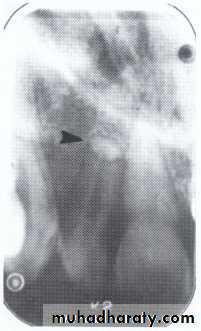

Dens in Dente (invaginated odontome) :

*It is an infolding of the outer surface of a tooth into the interior usually in the cingulum pit region of maxillary lateral incisors (tooth within a tooth).

*It is of 2 forms:coronal& radicular.

*Clinicaly varies from slight enlargement of cingulum

to a deep infolding that extends to the apex.

It has been classified into 3 major types:

*Type I:it is confined within the crown of the tooth and does not extend beyond the level of the external CEJ. *Type II :extends below CEJ ends in a blind sac, may or may not communicate with adjacent dental pulp. *Type III:extends through the root and communicates laterally with the periodontal ligament space through a pseudo-foramen or at the apical foramen . There is usually no communication with the pulp, which lies compressed within the root.*Most cases of dens in dente are discovered radiographically. It is more radiopaque than the surrounding tooth structure and can easily be identified.